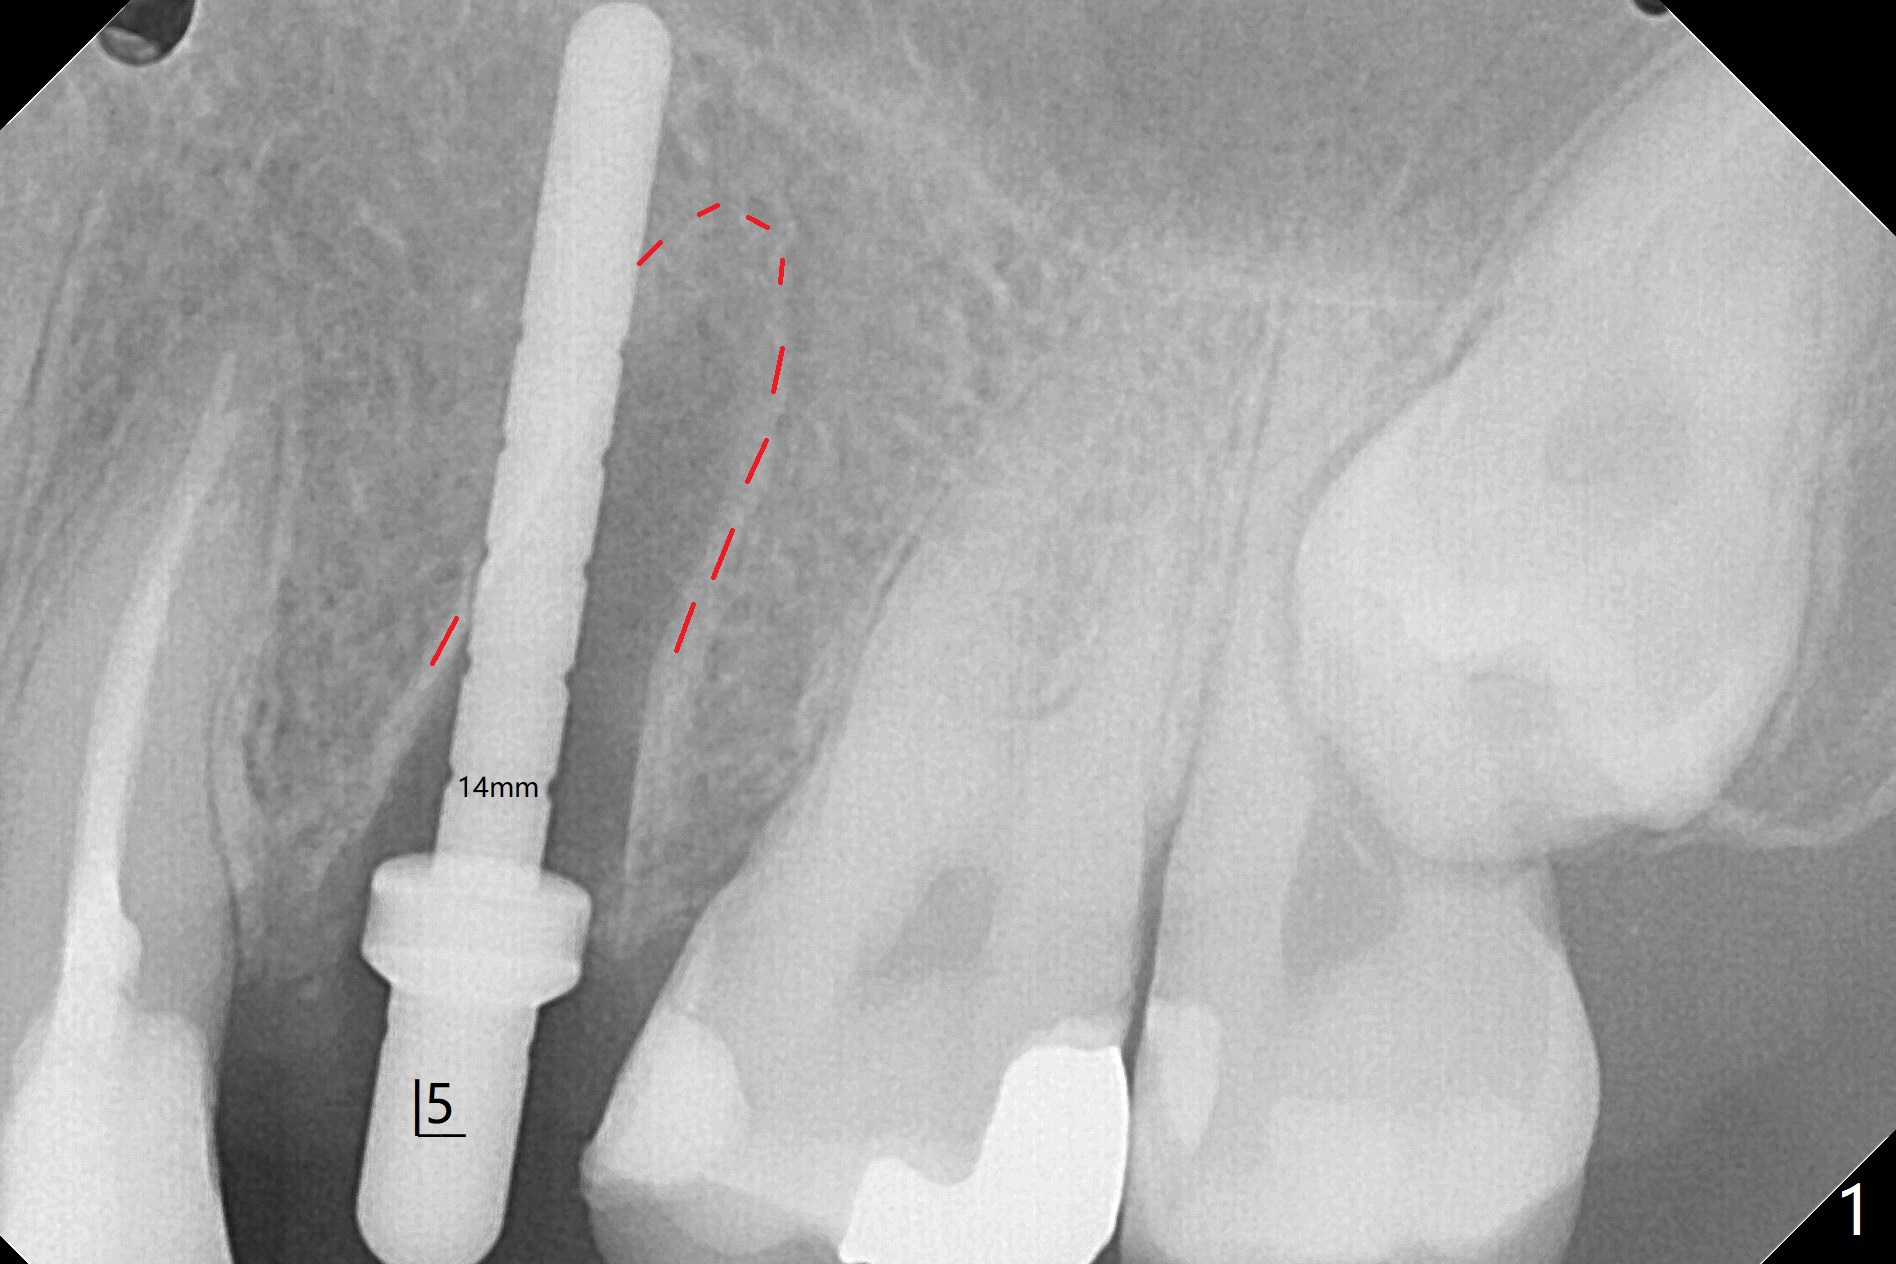

左上五牙齿长轴好像不理想,有意在即刻植牙过程中改之(图一),美中不足的是钻洞深度控制不好,太深了,